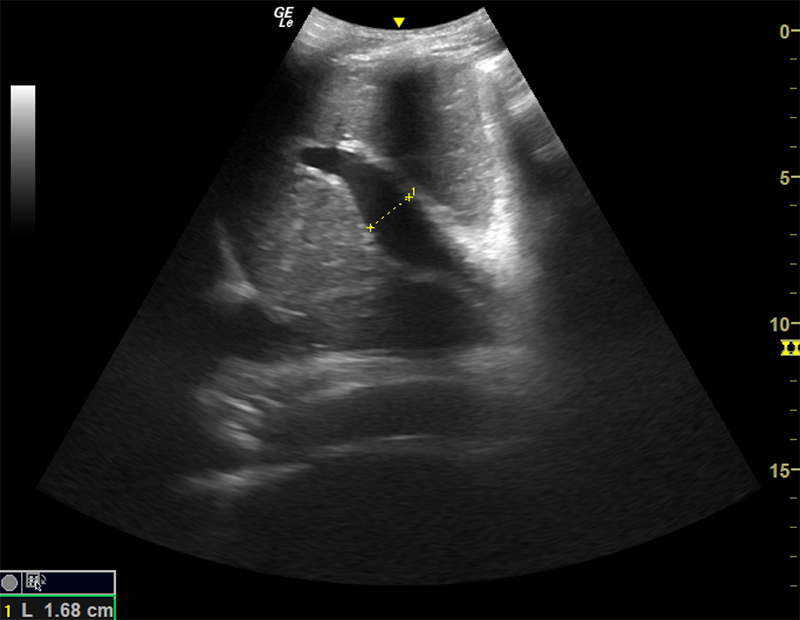

- Enlargement of portal vein (>14mm)

Figure 16. Dilated portal vein (>14mm) in the setting of portal hypertension.